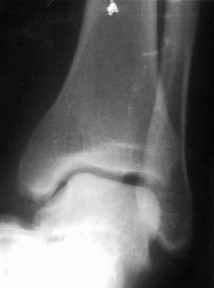

братился мужчина, 50 лет. Жалобы на боли в голеностопном суставе, периодическое подворачивание стопы вовнутрь.

Получил травму 5 лет назад.

При осмотре - признаки латеральной нестабильности, боли по ходу малоберцово-таранной, задней малоберцово-пяточной связки. Сделал стандартный Rg, и Rg с нагрузкой. В течение последнего года начали беспокоить боли в коленном, тазобедренном суставе. Как полагаю, это связано с нарушением биомеханики всей ноги. Если прооперировать и устранть нестабильность, пройдут ли эти боли (этот вопрос пациент задал сразу, как только услышал слово операция)?